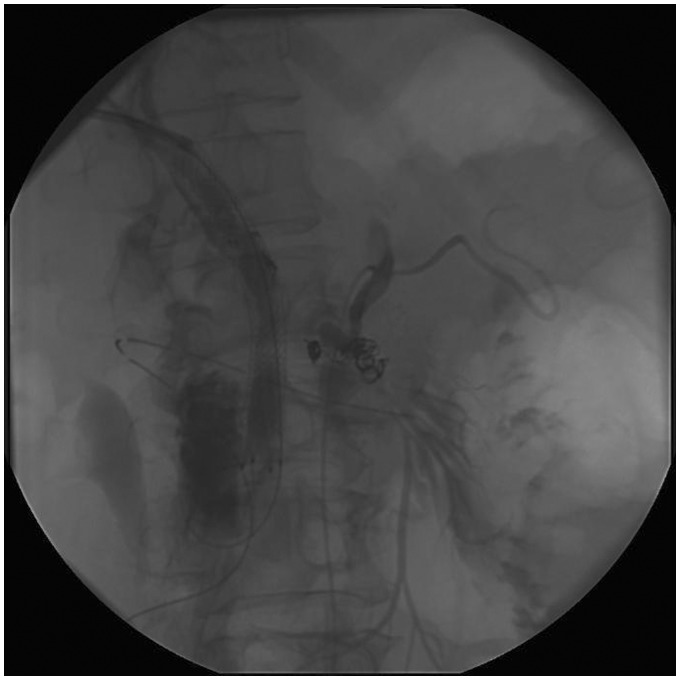

不可逆电穿孔(IRE)是一种消融技术,正在被研究作为胰腺癌的潜在治疗方法。然而,许多患者在胆管内放置金属支架,这被认为是IRE消融术的禁忌症。我们报告一个病例,在胰腺头部区域IRE消融术对患者进行金属支架导致严重的并发症。治疗后,患者出现了多种并发症,包括十二指肠穿孔和横结肠穿孔,以及肠系膜上动脉分支出血,最终导致患者死亡。因此,我们认为如果考虑在金属支架附近进行IRE消融,了解这一点是很重要的。

Irreversible electroporation (IRE) is an ablation technique that is being investigated as a potential treatment of pancreatic cancer. However, many of these patients have a metallic stent in the bile duct, which is recognized as a contraindication for IRE ablation. We report a case in which an IRE ablation in the region of the pancreatic head was performed on a patient with a metallic stent which led to severe complications. After the treatment, the patient suffered from several complications including perforation of the duodenum and transverse colon, and bleeding from a branch of the superior mesenteric artery which eventually lead to her death. Therefore, we believe it is important to be aware of this if an IRE ablation close to a metallic stent is considered.